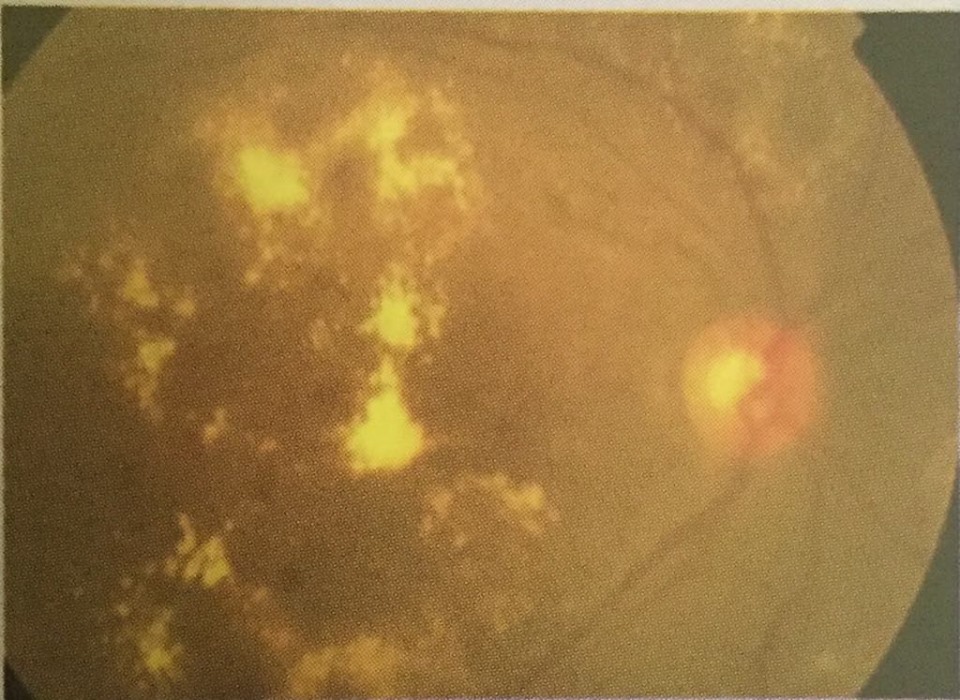

Hard exudate

Deep yellow with sharp margins, often circinate Diabetes, hypertension, von Hippel Lindau disease, radiation